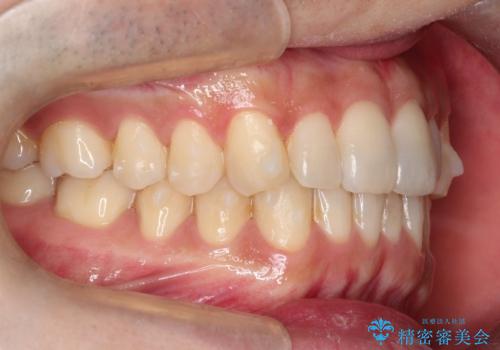

- 前歯の歯並びの改善を希望され来院された患者様です。

初診時の歯並びの状態としては、下顎に中等度のがたつき(叢生)がある状態でした。

抜歯は行わず下顎の奥のスペースを利用して歯をスライドする方法の他に親知らずの抜歯そして上下ともに歯列弓の拡大やディスキング(歯と歯の間の隙間を作る処置)を行い叢生を改善しました。

歯の大きさの不揃いが原因の正中のズレは、ディスキング量を調整することで合わせました。

矯正装置としてはマウスピースを使用しています。